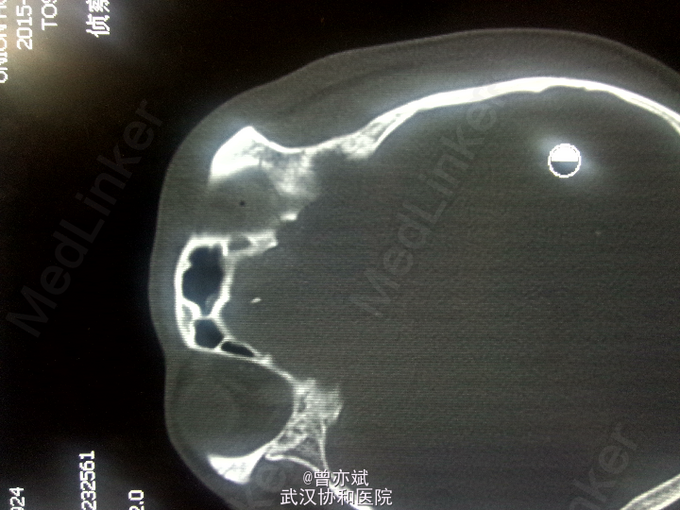

查体:T 36.9℃,P 70次/分,R 20次/分,BP 128/82mmHg,查体不合作,神志浅昏迷,营养发育良好,皮肤及淋巴结未及明显异常,头颅大小正常,无畸形,头发分布正常,左额部软组织损伤,心肺腹未及明显异常。双下肢无水肿,生理反射存在,病理反射未引出。 专科查体:神志浅昏迷,GCS评分3+3+4分,左侧瞳孔直径6mm,对光反射消失,右侧瞳孔直径4mm,对光反射存在,四肢肌力2级,生理反射存在,病例反射未引出。 辅助检查:外院及我院急诊CT示左侧额部硬膜外血肿。急诊CT:1、左侧额部硬膜外血肿,厚度为23mm;2、少量蛛网膜下腔出血;左侧额骨线性骨折累及左侧眶顶、内侧壁及眶突,左侧眼眶内侧壁局部凹陷,考虑为外上性改变,左侧筛窦积液、积血、蝶窦积液。